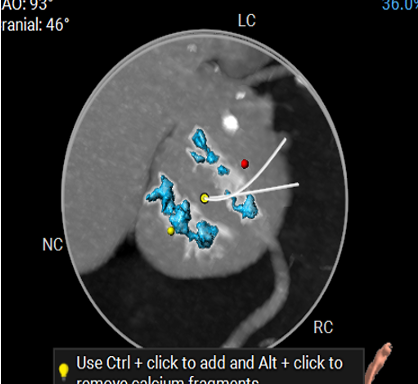

CT数据显示该患者为Type1型主动脉瓣。

冠脉高度测量

LEFT CORONARY

左冠开口高度14.0mm

RIGHT CORONARY

右冠开口高度13.1mm

冠脉开口及瓣叶长度评估

钙化分布:HU850钙化积分413mm³